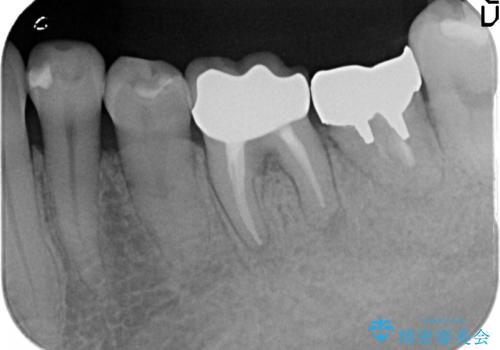

- 左下の銀歯が外れたので診て欲しいといらっしゃった方の症例です。

他院にて再装着したが不安なので、根管治療からやり直したいとのことでした。

再根管治療終了後、オールセラミッククラウンによる補綴を行いました。

今回用いたオールセラミッククラウンはジルコニアフレームという白い素材の上にセラミックを盛っているため、審美性が非常に高いのが特徴です。

また、ジルコニアは人工ダイヤモンドの材料にも使われているほど高い強度を持っており、そのためオールセラミッククラウンは審美性だけでなく、奥歯やブリッジの補綴も可能とするクラウンです。